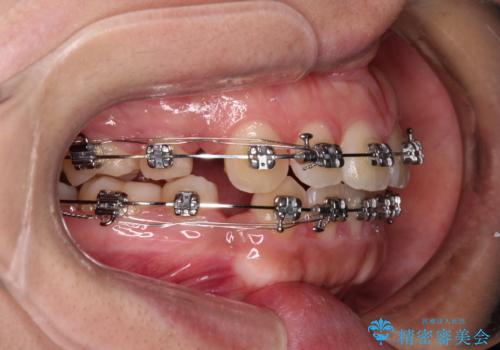

- メタルブラケット

上下の前歯が前方に突出していたため、上下左右の第一小臼歯4本を抜歯し、ワイヤー装置にて抜歯矯正を行うこととしました。